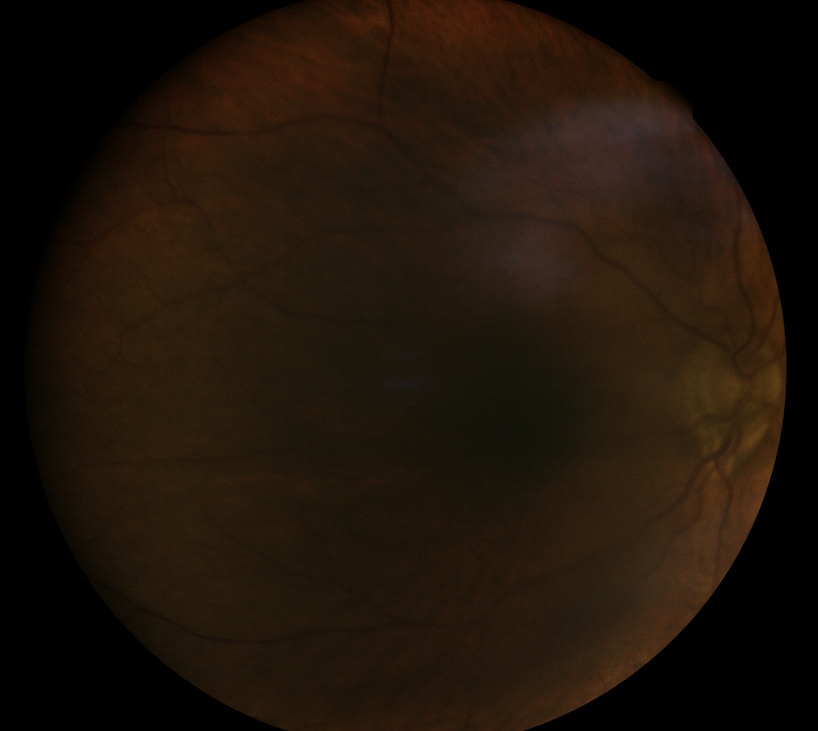

1) Cataract ++

Despite an important cataract with an invisible fundus of eye in Volk 90Δ or indirect ophthalmoscopy, Eidon manages to see the fundus of the eye.

Malgré une importante cataracte avec un fond d'oeil invisible en Volk 90∆ ou en ophtalmoscopie indirecte, Eidon arrive à apercevoir le fond d'oeil.

Nonostante significativa cataratta con un fondo invisibile in Volk 90Δ o oftalmoscopia indiretta, Eidon riesce a vedere il fondo.

- Eidon Retina

- Eidon retina